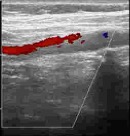

В статье представлен случай успешного хирургического лечения тромбоэмболии легочной артерии у пациентки с высоким риском ранней сердечной смерти на фоне парадоксальной эмболии, осложненной острым нарушением мозгового кровообращения. Криптогенное острое нарушение мозгового кровообращения в комбинации с тяжелой прогрессирующей правожелудочковой недостаточностью на фоне ТЭЛА обусловливает серьезные трудности при принятии решения в отношении тактики лечения у данных больных. Внутрисердечная локализация тромбоэмбола, угрожаемая развитием не только рецидива тромбоэмболии легочной артерии, но и парадоксальной эмболии требует незамедлительного выполнения комплекса дифференциально-диагностического обследования, направленного на верификацию патофизиологического механизма развития заболевания, что во многом определяет эффективность проводимого лечения. Анализ доступных литературных данных, приведенный в работе, а также анализ клинического случая позволяют выработать тактический алгоритм в этой группе пациентов и определить показания к открытому оперативному вмешательству.